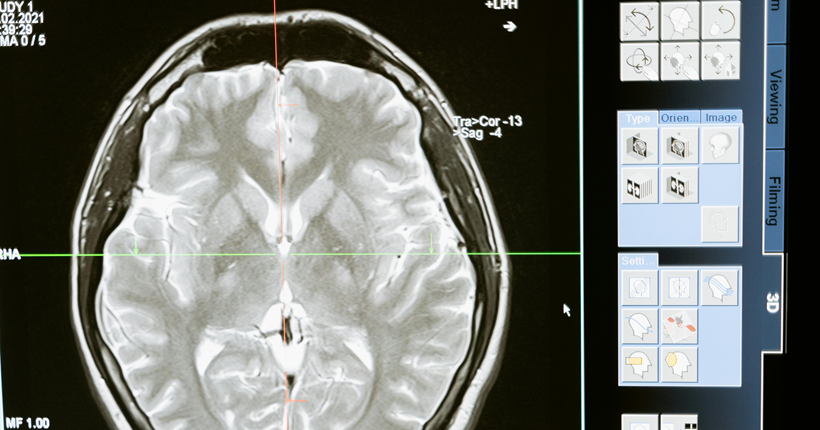

Factores de riesgo y biomarcadores de la enfermedad de Alzheimer

Julio Antonio Esquivel-Tamayo1, Arquímedes Montoya-Pedrón2 | 1 Doctor en Medicina. Residente de Tercer Año en Medicina Familiar. Doctorando en Ciencias Médicas. Diplomado en Medicina Natural, Tradicional y Apiterapia. Profesor Instructor. Universidad de Ciencias Médicas de Las Tunas. Policlínico Docente Manuel Fajardo Rivero. Las Tunas, Cuba. 2 Doctor en Ciencias Médicas. Especialista de Primer y Segundo Grado en Neurofisiología Clínica. Profesor e Investigador Titular. Jefe del Servicio de Neurofisología del Hospital General Dr. Juan Bruno Zayas Alfonso. Universidad de Ciencias Médicas de Santiago de Cuba. Santiago de Cuba, Cuba. La enfermedad de Alzheimer, constituye un problema sanitario y social de gran magnitud; precisa de diagnóstico y terapéutica precoces. Dispersos estudios de diversa metodología se refieren a la predicción de la demencia a partir de factores de riesgo. No obstante, existen insuficientes investigaciones que analicen en conjunto factores de riesgo y biomarcadores y los asocien; lo que ha limitado la posibilidad de acciones preventivas y terapéuticas precoces en pacientes en riesgo. Se realizó una revisión sistemática de la literatura con el objetivo de analizar los factores de riesgo y los biomarcadores de la enfermedad de Alzheimer. Se realizó una búsqueda de los términos: "demencia/ dementia", "enfermedad de Alzheimer/ Alzheimer’s disease" "factor de riesgo/ risk factor", "biomarcador/ biomarker", en las bases de datos: PubMed/Medline, Scopus, Scielo, Lilacs y mediante el buscador Google académico; se consultaron documentos no publicados. Se clasificaron los resultados de la búsqueda mediante el examen del título y resumen. De 154 investigaciones encontradas se incluyeron revisiones, metaanálisis, estudios observacionales y ensayos publicados desde el año 2017 hasta el 2023, en idioma español, inglés y portugués. Se excluyeron trabajos duplicados, libros o capítulos de libros, estudios cualitativos, que no se relacionaran con el tema o sin acceso al texto completo. Tras la aplicación de los criterios, se obtuvieron 32 estudios observacionales, 23 revisiones, 12 metaanálisis, y 3 ensayos. Se revisaron los documentos completos para verificar el cumplimiento de los criterios de inclusión. Los principales factores de riesgo encontrados son edad avanzada, menor educación, poca actividad física, hábito de fumar, consumo excesivo de alcohol, hipertensión arterial, diabetes, obesidad, depresión, pérdida o disminución de la audición, aislamiento social, los traumas craneales y la contaminación ambiental. Los biomarcadores fundamentales son: los marcadores que se utilizan en los estudios de neuroimágenes como la tomografía por emisión de positrones (PET) Amiloide, PET tau, PET con fluorodesoxiglucosa (FDG); y en líquido cefaloraquídeo y plasma: Aβ42, Aβ42/Aβ40, p tau 217, p tau 181, proteína gliofibrilar ácida (GFAP), y neurofilamentos de cadena ligeras. Se reconoció el uso de los parámetros cuantificados en el P300 como biomarcadores complementarios clasificadores de la presencia y del nivel de disfunción cognitiva de etiología enfermedad de Alzheimer posible. La mayoría de los estudios analizados, aunque abordan con profundidad la relación de los factores de riesgo y la enfermedad de Alzheimer, tienen limitaciones al asociar unos factores con otros, o con biomarcadores. Se requieren estudios longitudinales, a partir de la presencia de los factores de riesgo asociados a biomarcador, desde edades pregeriátricas en pacientes sanos, que tengan como salidas el deterioro cognitivo y el desarrollo de la demencia, para construir un modelo de predicción. Leer el artículo completo